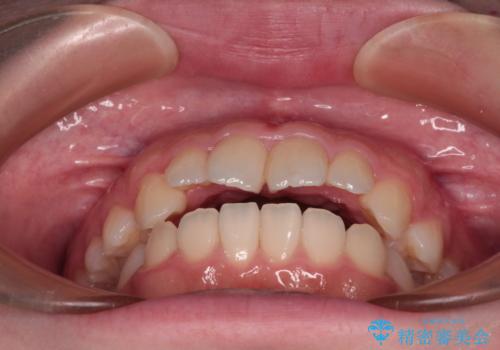

- 前歯が開いて飛び出していることを気にして来院された患者様です。

舌の突出癖により上下前歯は接触できず、更には前方に押し出されて出っ歯になっている状態でした。

上下左右の第一小臼歯4本を抜歯し、ワイヤー装置での抜歯矯正を行っていくのですが、原因である舌の突出癖を改善しないことには治療がうまく進められないため、舌のトレーニングを徹底するよう指導していくこととしました。